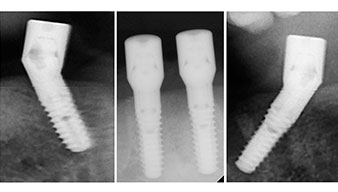

Les piliers angulés (35°) ont été vissés pour compenser la divergence des implants distaux. Ainsi, le profil

d'émergence de tous les implants doit être le plus perpendiculaire possible par rapport au plan occlusal. Il s'agit

d'une condition préalable à la pose en occlusion de la prothèse provisoire puis permanente (Fig. 15 et 16).